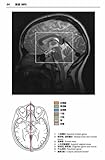

こんなときどうする?アロマセラピーケアガイド―実例付き!家庭でできる症状別ケア ![]() 価格: 1,890円 レビュー評価:4.5 レビュー数:10 アロマの家庭の医学的な本だと思います。 最初手にした時は、カラーでなく、教科書的な文章ばかり。少しばかりのイラストは臨床的で専門的なものが多く、がっかりしました。 でも読んでいくうちに、知っておくべき身体の症状や、解剖・生理学的な解説もなされていて、根拠がしっかりしています。じっくり読んでも、その時の自分の症状にあてはまるところだけを読んでも、理解しやすいです。 紹介されている事例や精油も日常的なもの。 少しでもアロマに興味があれば持っていると知識が深まり、より親しみが持てると思います。 |